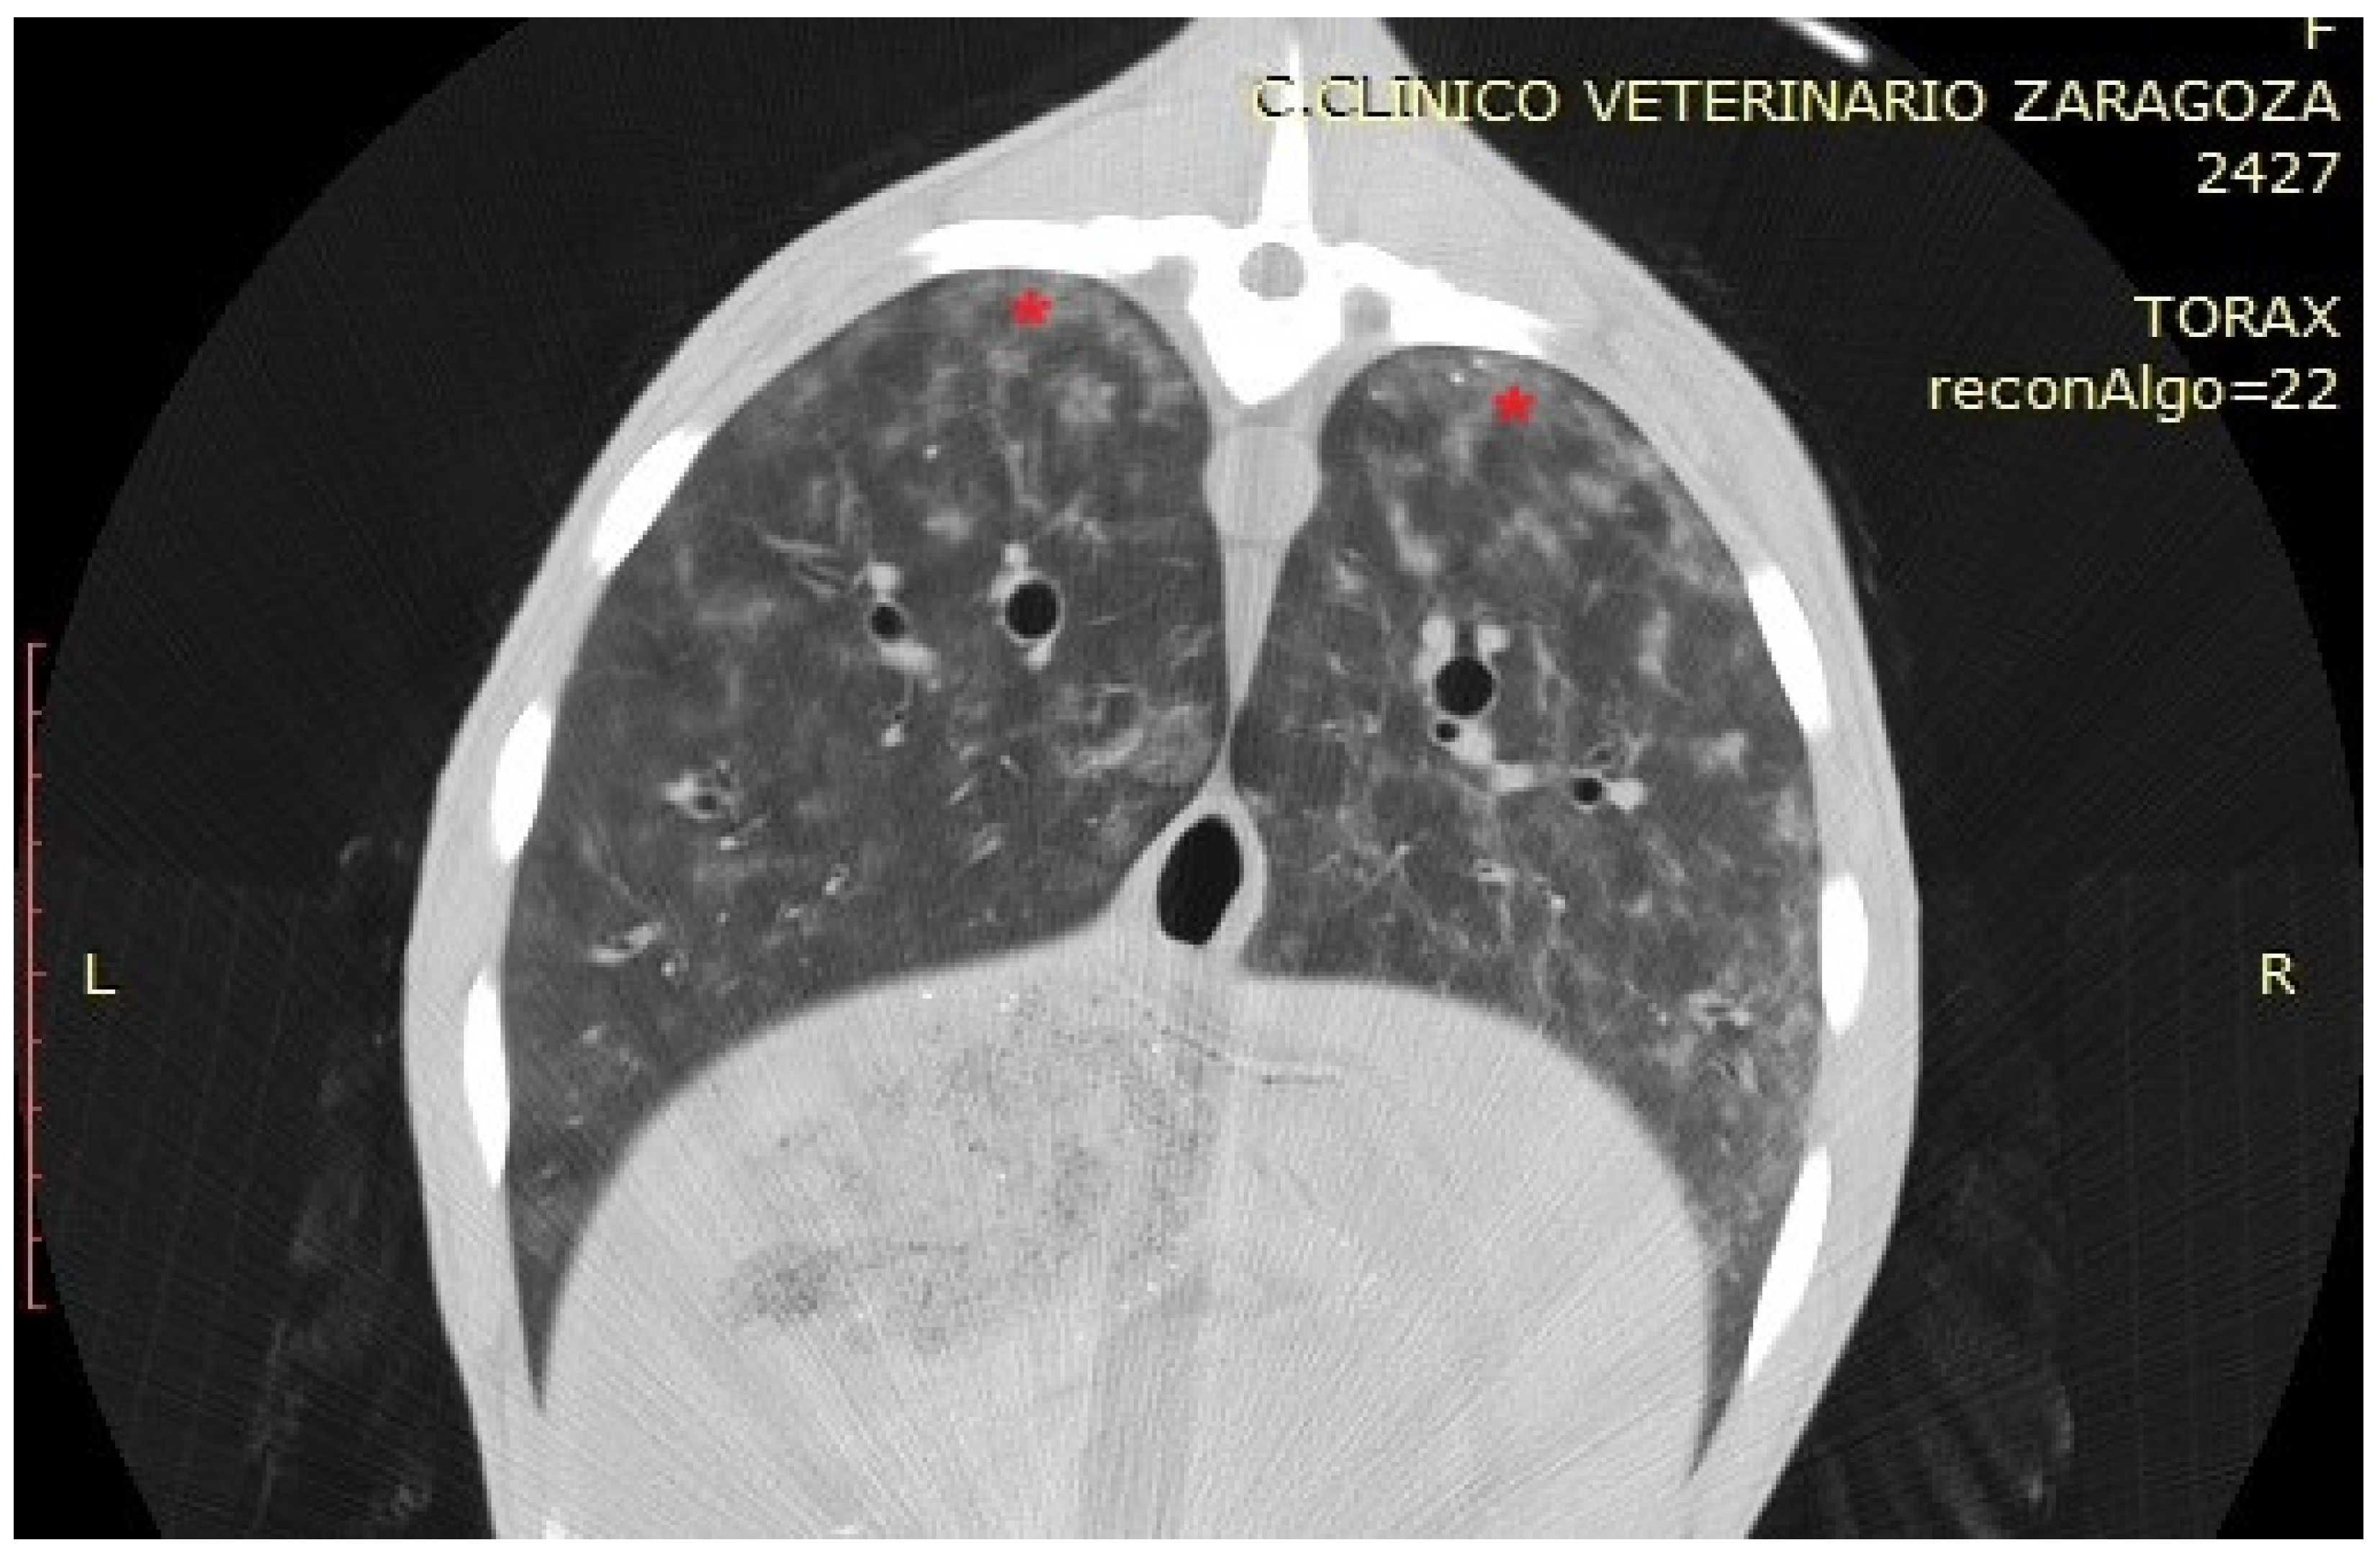

3.3.3. Chronic Form of Ovine Respiratory Complex (ORC)

| Chronic ORC | Lobar consolidations, some collapsed regions | 40 to 60 HU | Hyperdense, airless areas; alveolar collapse and parenchymal remodelling |